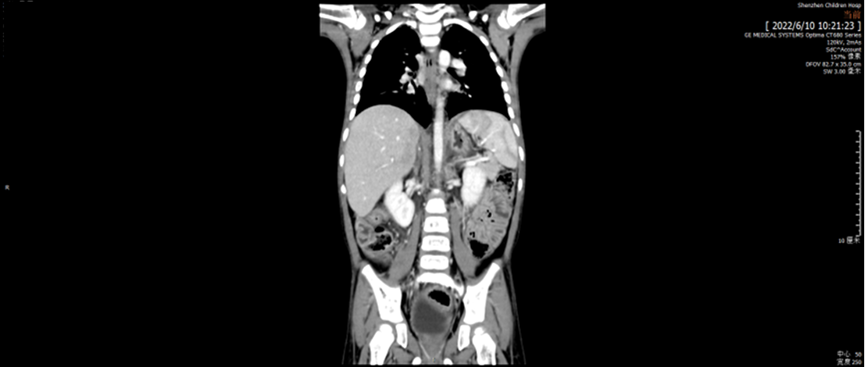

2022.06 巩固治疗后疗效评价:

腹部CT提示原肝脏低密度灶未见显示。骨髓涂片、流式细胞学及活检均未见肿瘤细胞。疗效评价为CR。